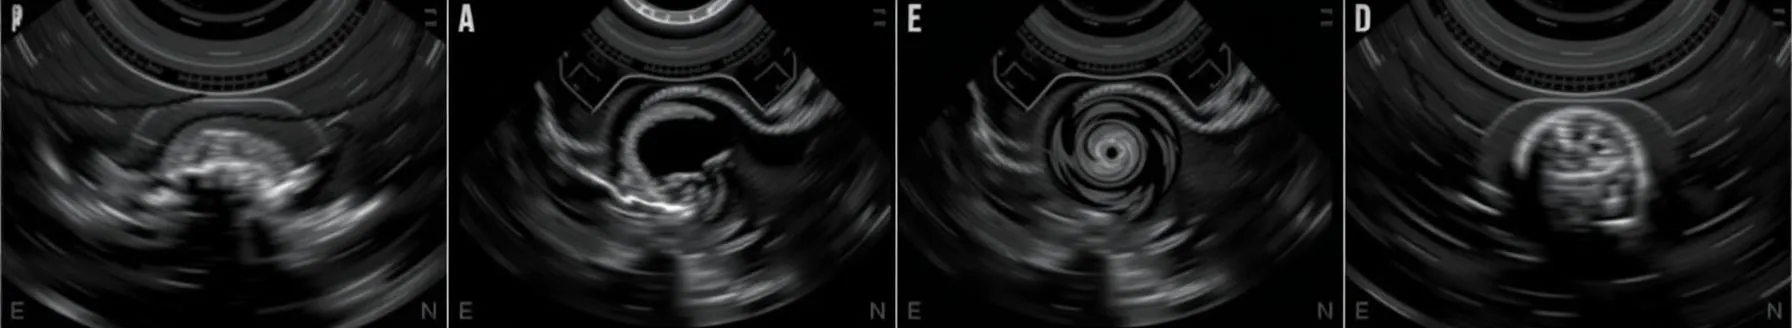

- Echocardiography allows visualization of heart valves, wall structure, fluid presence, and air cavities, assisting in cardiac surgery assessments. Transesophageal echocardiography (TEE) is now commonly used, offering a comprehensive view. It also aids in identifying aortic dissections in patients presenting with severe chest pain, looking for tell-tale signs like a double shadow.